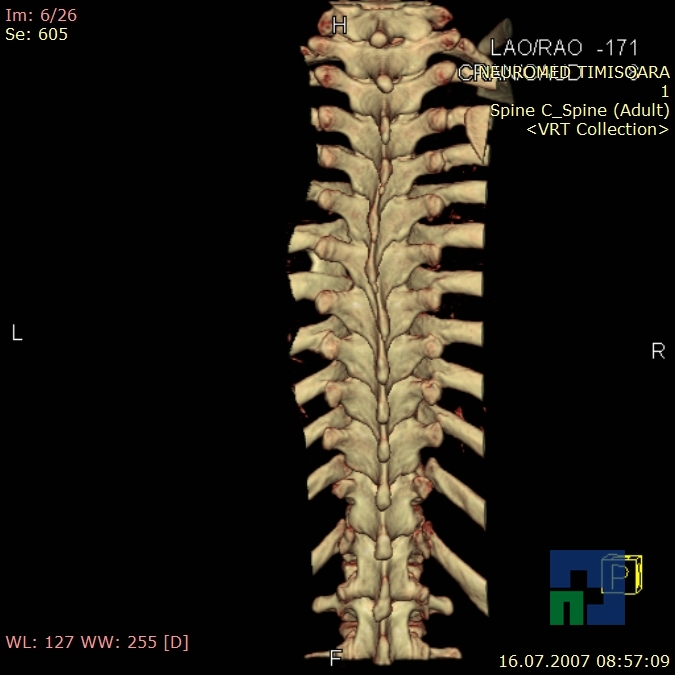

- Diagnosticul fracturilor:

- Unice

- Multiple

- Cu înfundare

- Complexe cranio-sinusale

- Complexe cranio-etmoidale

- Complexe cranio-orbitare

- Complexe cranio-faciale